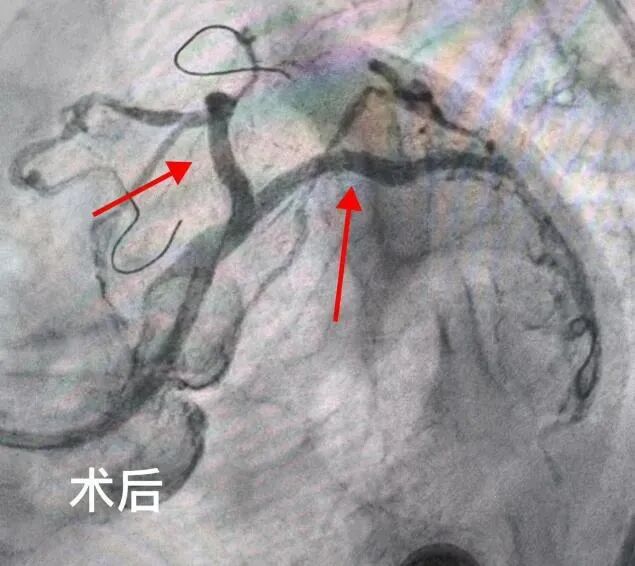

2025年5月,吉林市人民医院心内五病区收治了一位70岁的老年女性患者。该患者反复心绞痛1年,近3天症状加重。入院后,冠脉造影检查明确显示其存在严重的三支血管病变。通常情况下,冠脉搭桥手术是此类患者的首选治疗方案,但家属综合考虑患者年龄和身体状况,最终选择冠脉介入治疗。经心内五病区张金子主任团队审慎评估,决定分两次为患者实施支架植入术。

第一次手术顺利完成,在患者右冠状动脉植入两枚支架,心绞痛症状有所缓解,但仍反复发作。经过两周的精心调整,5月25日,患者再次入院接受第二次支架植入手术。然而,术后返回病区时,患者突发严重并发症——因剧烈恶心呕吐,吐出大量鲜血。由于患者既往有慢性胃炎病史,这一突发状况导致其病情急剧恶化,生命危在旦夕。 专 家 介 绍 吉林市人民医院心血管内科五病区主任 熟练处理各种疑难复杂病变,急性心梗介入治疗,慢性闭塞病变(CTO),左主干病变,分叉病变,血栓病变,口部病变,迂曲钙化病变,桥血管病变等介入治疗,熟练掌握各种分叉支架术式(crush,cullote),IABP(主动脉球囊反搏泵)辅助下高危病人介入治疗,IVUS(血管内超声),OCT(光学相关断层扫描技术)及FFR(冠脉血流储备检查)等各种设备及腔内影像学检查,为一名成熟独立术者。 以第一申请人申请市级课题一项;共发表论文11篇,其中核心期刊4篇;参与“国家级自然基金”课题1项;2018年于北部战区总医院心内科完成冠脉介入基地学员培训并获得冠脉介入资质证书;2020年于北部战区总医院心内科完成心血管专科医师培训,同年取得中国医师协会颁发的专科医师规范化培训合格证书。2022年于北部战区总医院心内科完成培训并获得结构性心脏介入资质证书。 吉林市昌邑区人大代表;吉林省老年心血管预防康复委员;吉林省中西医结合学会第一届心衰防治与康复专业委员会委员;2022年昌邑区十九届人民代表大会代表;2022年度吉林市昌邑区优秀人大代表;2022年吉林市统战最美统战人新阶层创新之星;2023年度吉林市昌邑区优秀人大代表。